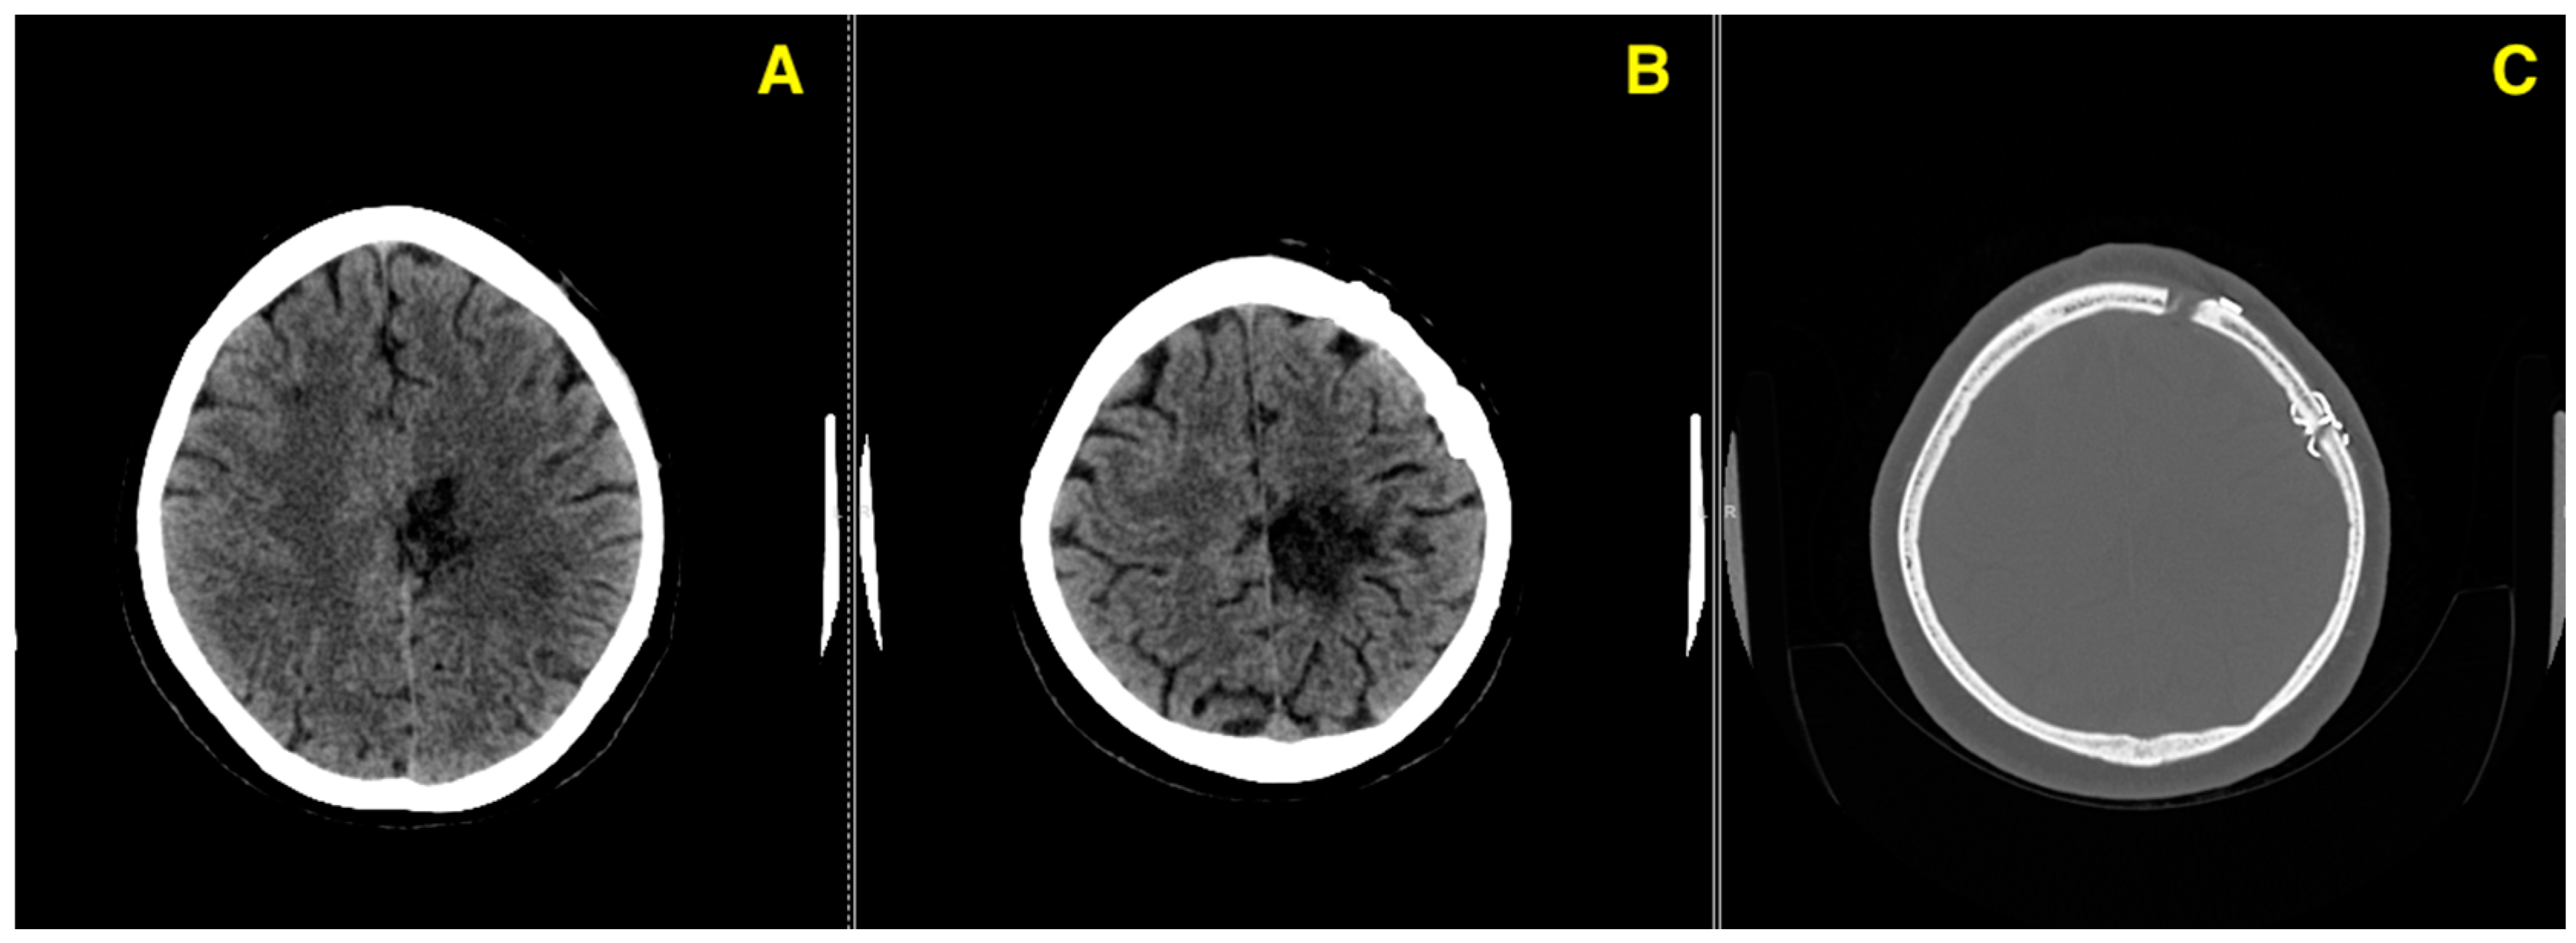

Challenging Management of a Rare Complex Cerebral Arteriovenous Malformation in the Corpus Callosum and Post-Central Gyrus: A Case Study of a 41-Year-Old Female

2. Case Presentation